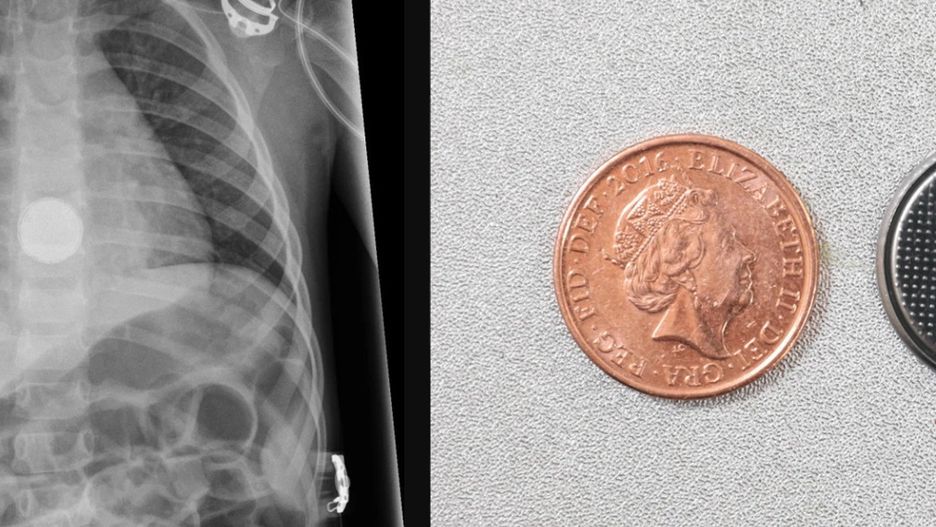

Elsie-Rose Duffy miała dwa latka, gdy jej życie zawisło na włosku. Dziewczynka trafiła do szpitala z bólami brzucha. Prześwietlenie wykazało obecność baterii w przełyku dziecka.

Dziewczynka połknęła baterię wielkości monetyDziewczynka połknęła baterię wielkości monety

Elsie-Rose trafiła do szpitala z powodu niewyjaśnionego silnego bólu brzucha. Lekarze, którzy wykonali badania, byli w szoku. Na prześwietleniu widać było baterię, która utknęła w przełyku.